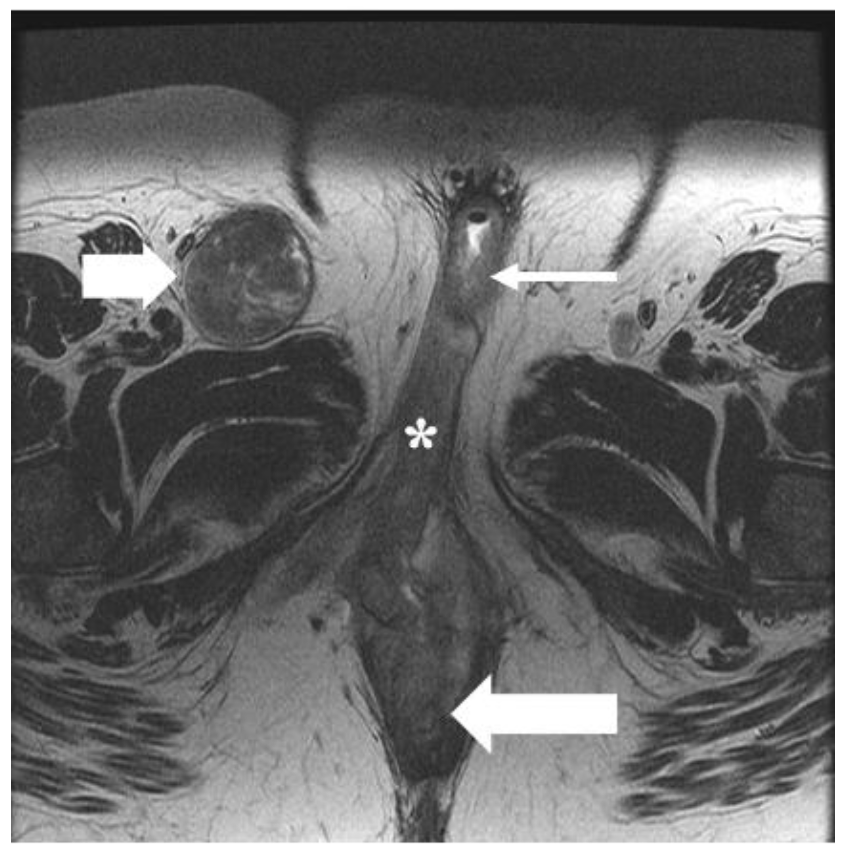

5.3. Stage III

5.4. Stage IV